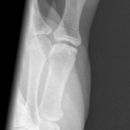

Bennett Fraktur